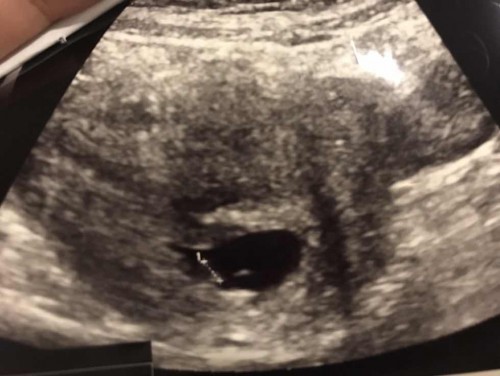

ขอดูใบซาวด์ของแม่ๆหน่อยคะ ว่าน้องขนาดไหนกันแล้ว แม่ไปหาหมอตอน ตามแอฟ7วีค แต่ซาวแล้ว 6วีค2วันคะ